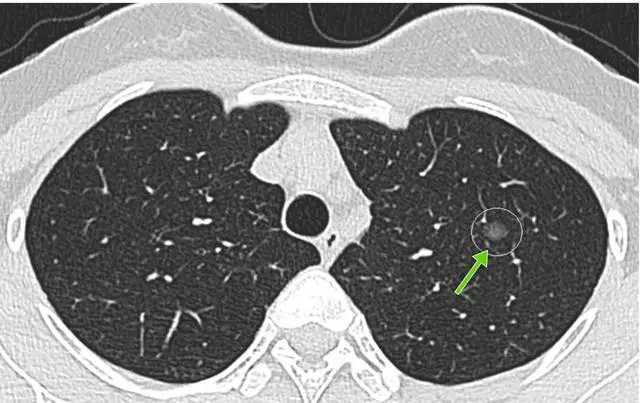

肺转移瘤同样可以表现为双肺多发的小结节影。一般情况下,肺转移瘤在CT上表现为:双肺多发大小不等的实性结节影,对于早期转移瘤,是可以表现为微小结节的,同时结节分布也没有特异性,一般是随机分布,双肺任何地方都可以出现。

同时需要提醒的是,肺转移瘤一般都有原发恶性肿瘤的病史。比如说,如果一位患者之前有肝癌的病史,那么在做胸部CT检查的时候发现了双肺多发的小结节影,那么这个时候就需要首先考虑是肺转移瘤了;相反,如果一个患者没有原发恶性肿瘤的病史,那么一般都不会首先考虑肺转移瘤。